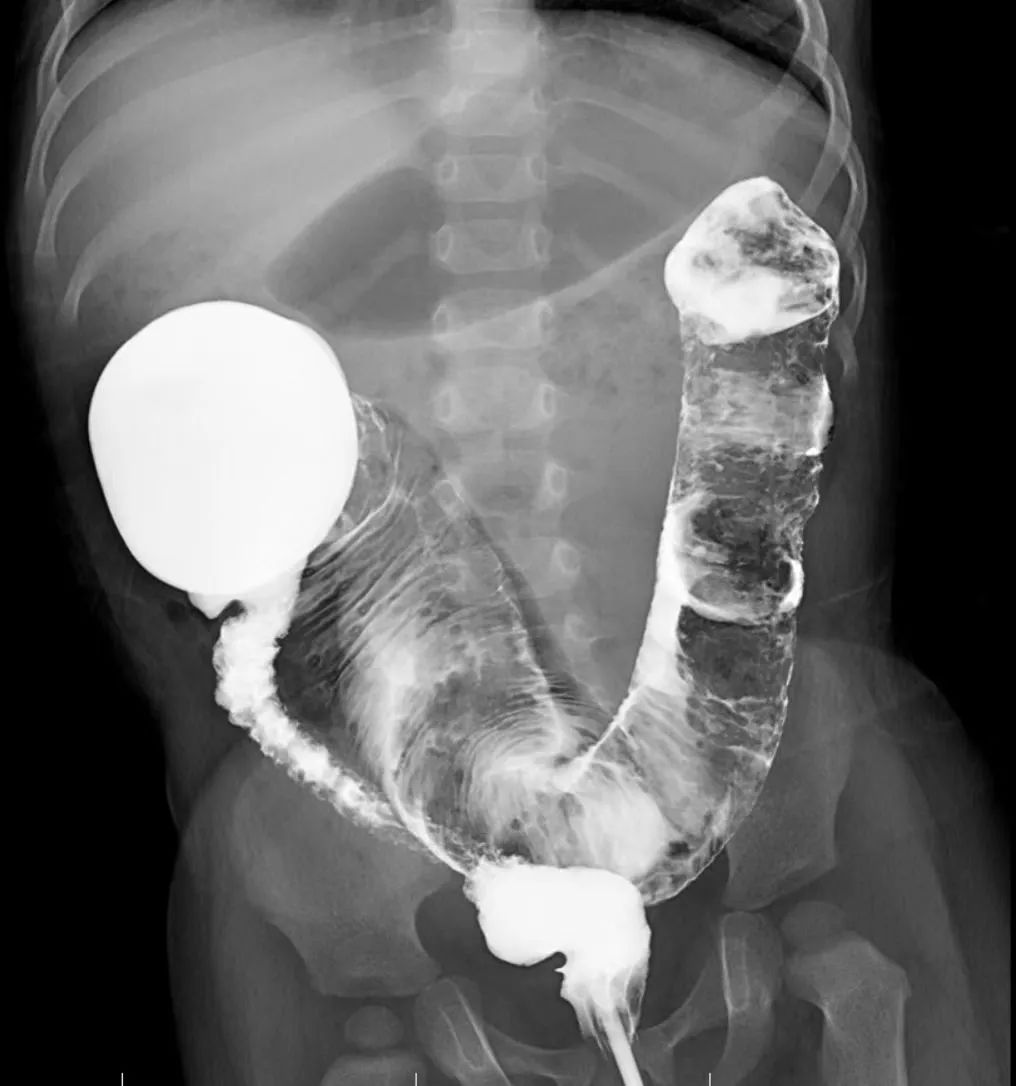

而先天性巨结肠则是靠近菊花那一段肠管因为缺少了神经节细胞,长期处于痉挛细小不干活的状态,肌肉团队缺乏肠道神经的配合,便便到了这里就很难通过而在上方正常的结肠里玩起大塞车,久而久之上方的结肠就如同吹气球般扩张肥厚,变成了「巨结肠」。

看着病历本上孩子因病变肠管长,扩张明显,已经不能做微创手术的诊断。李女士一家最终无奈决定,接受医生建议行开放性手术:在孩子肚子划开一道长长的口子,再把坏死的肠道切掉。

手术利用 3 个 4 mm 切口作为通道,其中一个通道插入腹腔镜的摄像探头,孩子肚子里病变的肠管在显示器上显示得清清楚楚。

这时,周小渔主任从另外两个通道插入微创手术专用的手术器械,在腹腔镜辅助下将发生病变的肠管全部切除,总长约 35 cm,手术全程几乎没有出血。